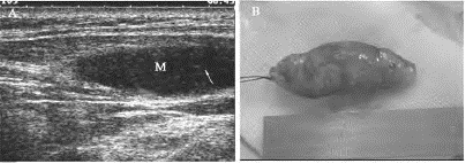

1.39.7七、其他骨、关节、肌腱、周围神经及软组织疾病